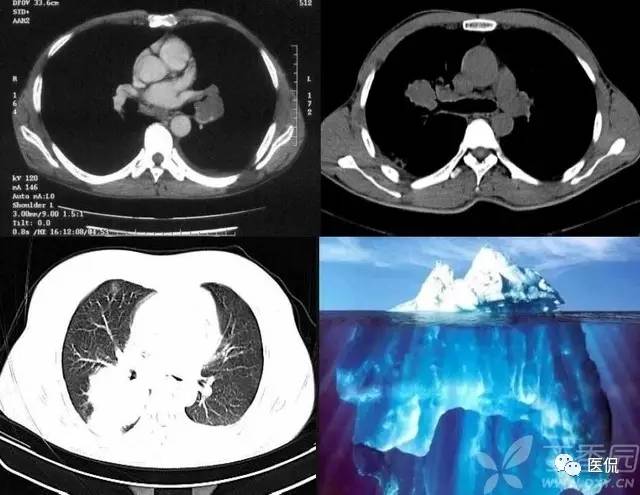

冰山征

yc023711战友发了这样一个帖子:右肺上叶站位,有病理【病理结果已公布】 - 丁香园论坛,病理是肺类癌。其中有网友谈到了“冰山征”的问题。个人感觉,冰山征并非肺类癌所独有,凡是病变沿支气管粘膜下生长,并向粘膜内侵犯的病变都可能出现这一个征象,所以小细胞肺癌可以出现这种表现。

当然,因为支气管肺类癌常表现为支气管内肿块,肿块可以向外生长侵犯邻近的肺实质,有时表现为支气管腔外部分病灶大于腔内部分,CT能够清楚显示肿物在支气管腔内和腔外的部分,此征象也就是所谓“冰山征”。病灶较大并向周围侵犯邻近肺组织时CT可见此表现,此征象有助于周围型肺不典型类癌的诊断。显然,典型肺类癌同样可以表现这一征象。

要说明一点的是,类癌和小细胞肺癌其实是同一种类型,只是其分型不同而已。就如肺癌可以分为低分化,中分化和高分化一样。小细胞肺癌就像是一个低分化的肺癌,而类癌就是较小细胞肺癌分化好的一种病变,它们是同门兄弟,性格不同。下边用病例和图示说明“冰山征”,不过,下边病例的病理都是小细胞肺癌: